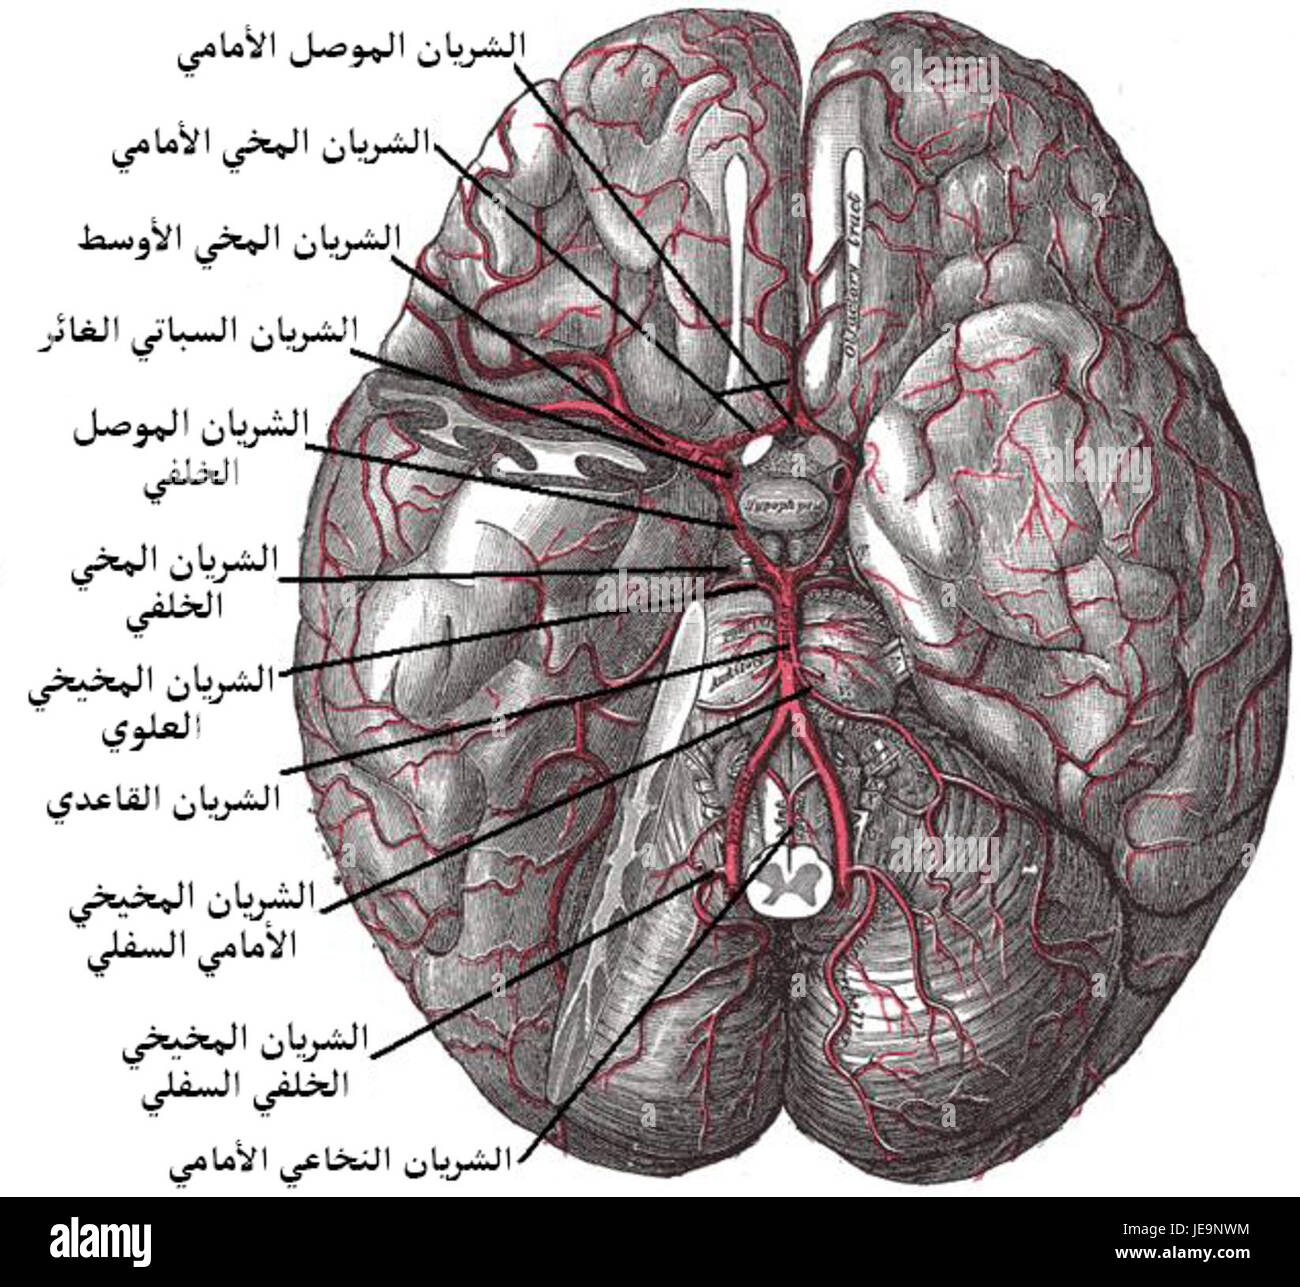

RFR3P9KW–Illustration der Blutversorgung des Gehirns. Das Gehirn hat wenig Kapazität, Nährstoffe zu speichern, aber es braucht eine hohe Versorgung mit Sauerstoff und Glukose.

RMJE9NWM–Dieses anatomische Bild zeigt die Arterien unter dem Gehirn, einem wichtigen Teil des menschlichen Kreislaufsystems. Die Arterien sind dafür verantwortlich, das Gehirn mit Blut zu versorgen und seine Funktion zu gewährleisten. Die Nahansicht hilft beim Verständnis ihrer Struktur und Rolle für die Gesundheit und Funktion des Gehirns.